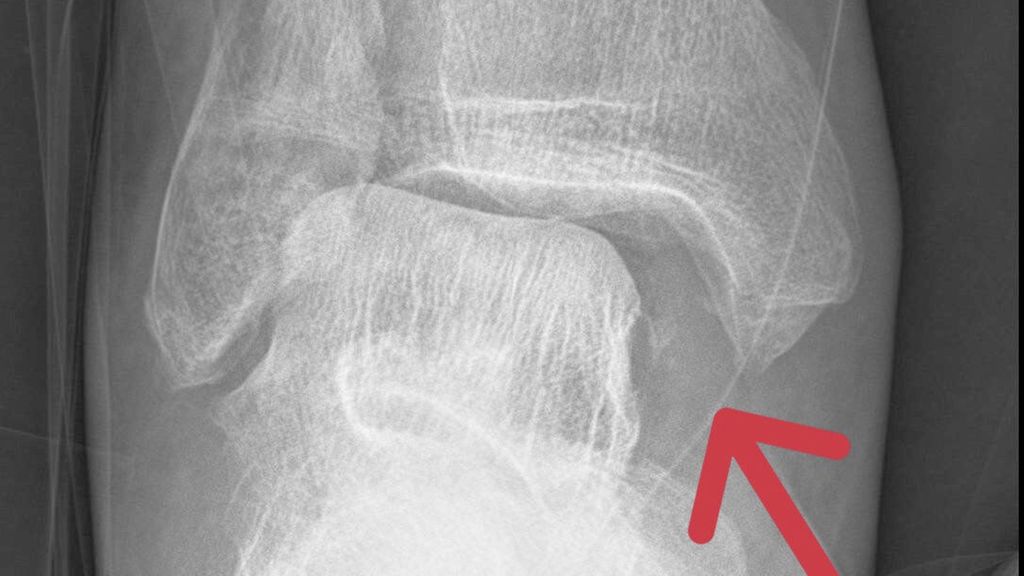

Als Standarddiagnostik erfolgt eine Röntgenaufnahme des Sprunggelenkes in zwei Ebenen. Die a.p-Aufnahme wird in 15–20° Innenrotation des Unterschenkels (Mortise-View) durchgeführt. Zur Beurteilung der Integrität des Deltabandes ist der Abstand zwischen Sprungbein und der lateralen Kortikalis des Innenknöchels („medial clear space“, MCS), entscheidend. Bei Werten <4mm ist das Deltaband intakt und die Fraktur stabil. Ist der MCS größer als 4mm oder gibt es klinische Zeichen einer Deltabandverletzung, muss weitere Diagnostik zur Feststellung der Stabilität durchgeführt werden.

Die Beurteilung des MCS in sogenannten „Stresstests“ mit forcierter Außenrotation des oberen Sprunggelenkes ist schwer objektivierbar und die Tests werden von Patienten nicht gut toleriert. Beim „Gravity-Stresstest“ wird ein Röntgen des Sprunggelenkes bei seitlich liegendem Patienten unter Einfluss der Schwerkraft durchgeführt, wobei die resultierende Außenrotation bei gerissenem Deltaband zu einer Erweiterung des MCS führt. Die Einführung der beiden Tests führten zu einer Reduktion der operativen Versorgtung von Außenknöchelfrakturen. Einige Studien haben jedoch gezeigt, dass ein Großteil der in den „Stresstests“ als instabil klassifizierten Frakturen unter physiologischer Belastung stabil ist. Bis zu 90% der Patienten mit einem positiven Befund im „Stresstest“ zeigen in der MRT-Untersuchung nur eine Teilruptur des Deltabandes.

Eine weitere Möglichkeit ist die Röntgenaufnahme im Stehen unter Vollbelastung nach 5–10 Tagen. Zeigt sich hierbei ein unauffälliger MCS, werden in der Literatur gute klinische Ergebnisse bei konservativer Behandlung beschrieben. Dawe et. al stellten fest, dass der „Gravity-Stresstest“ bei Außenknöchelfrakturen signifikant häufiger positiv ausfällt als der Röntgenbelastungstest (45% vs. 3,7%). Dementsprechend höher war die Anzahl der operierten Patienten und der damit verbundenen Komplikationen. In der Studie von Holmes et. al wurden bei 51 Patienten mit einem MCS <7mm (∅ 4,42mm) im „Gravity-Stresstest“ normale Werte in der Röntgenuntersuchung in Vollbelastung beobachtet. Diese Patienten wurden konservativ behandelt und zeigten gute klinische und radiologische Resultate. 90–98% der isolierten Außenknöchelfrakturen können trotz positiver „Stresstests“ oder klinischer Zeichen einer Instabilität bei negativem Röntgenbelastungstest konservativ mit gutem Outcome behandelt werden.